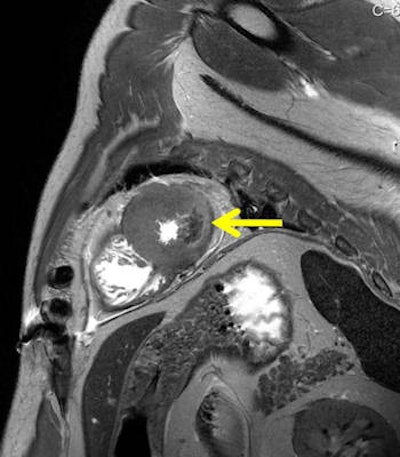

Peracute myocardial infarction in postmortem MRI (death occurred after minutes to one hour). A T2-weighted short axis image presents with a local hypointensity within the lateral wall without hyperintense edematous margin. Autopsy aspect of the specimen showed no visible alteration within the affected myocardium (not shown). Histology also failed in demonstrating ischemic alterations (not shown). Dissection of the coronary artery system revealed a fresh soft plaque rupture with intimal hemorrhage within the circumflex coronary artery (not shown).Sudden cardiac death happens mainly due to ventricular tachycardia with no direct findings in the heart in autopsy or histology as speed of death leaves insufficient time for recognizable myocardial changes. Jackowski's most recently published study demonstrates that unenhanced MR can show peracute myocardial infarctions even in the absence of a myocardial autopsy finding, and when histology may fail to show ischemic alterations.